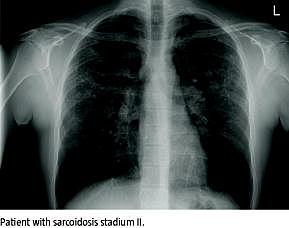

Journaler fra infliximabbehandlede sarkoidosepatienter blev gennemgået, og effekten af behandlingen blev vurderet ud fra ændringer i lungefunktionsundersøgelse (forced expiratory volume in the first second (FEV1), forced vital capacity (FVC), total lung capacity (TLC) og diffusion capacity for carbon monoxide (DL CO), Pangiotensin-converting enzyme (P-ACE) og P-interleukin-2 (P-Il-2) samt røntgen af thorax (stadium I-IV). Effekten af infliximab på ekstrapulmonal sarkoidose er beskrevet separat for okulær og kutan sarkoidose.

Tolv patienter (syv mænd og fem kvinder) med symptomer fra lungerne (n = 9), øjnene (n = 2), huden (n = 2), øsofagus (n = 1), nyrerne (n = 1), knoglemarven (n = 1), næsen (n = 1) og perifere lymfeknuder (n = 1) blev behandlet med infliximab enten på grund af manglende respons på traditionel immunsupprimerende behandling (n = 2), bivirkninger hertil (n = 2) eller en kombination heraf (n = 8). Yderligere karakteristik af populationen kan ses i artiklens Tabel 1 . Patienter med pulmonale symptomer opnåede en gennemsnitlig stigning i procent af forventet og i observerede værdier efter behandling med infliximab: ΔFEV1 (4,38 procentpoint og 0,15 l), ΔFVC (7,12 procentpoint og 0,35 l), ΔTLC (5,68 procentpoint og 0,35 l) og ΔDL CO (7,10 procentpoint og 0,84 mmol/kPa/min). Seks patienter havde før behandlingen med infli-ximab forhøjet P-ACE og/eller P-Il-2; deres middelværdi blev beregnet, og begge markører faldt til referenceintervallet efter endt behandling. En patient med radiologisk stadium I opnåede efter endt behandling et normalt røntgen af thorax, mens de andre patienter havde uændret radiologisk stadium. Effekten af infliximab på okulær sarkoidose viste sig ved sygdomskontrol af den uveale inflammation uden samtidig behov for steroid og for kutan sarkoidose ved regression af de kutane elementer. Endelig rapporterede alle patienter om en subjektiv effekt af behandlingen.